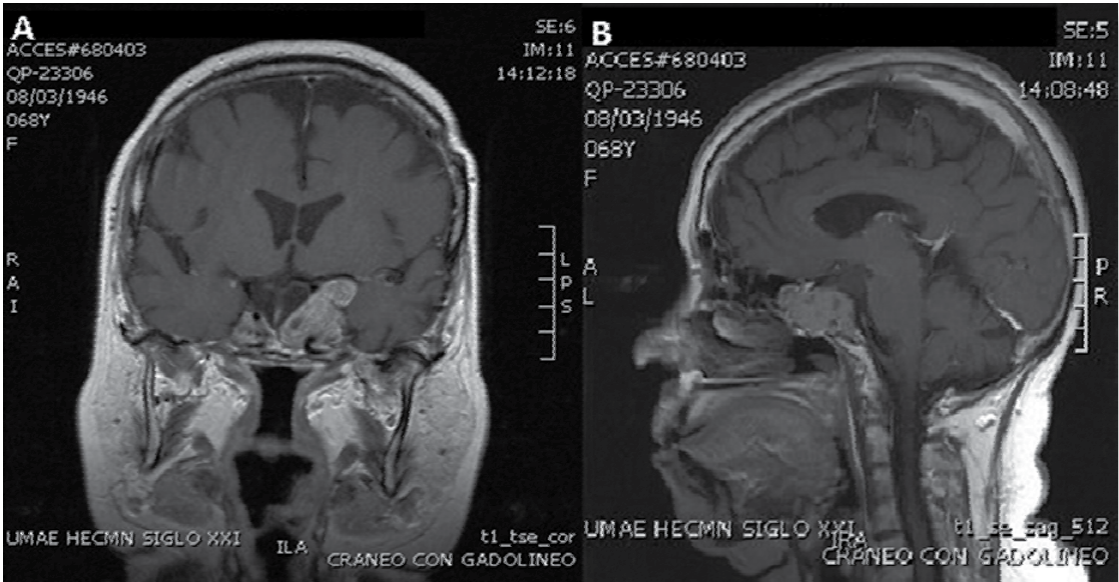

Por motivos inherentes a la paciente, se perdió vigilancia posquirúrgica. Doce años después regresó a nuestra Unidad Médica de Alta Especialidad, enviada desde su lugar de origen, por nueva pérdida del campo visual y cefalea holocraneana de intensidad 8 a 10 en escala visual análoga (EVA). Al retomar el caso, se corroboró hemianopsia bitemporal con campimetria por confrontación y digital; se solicitó un control de resonancia magnética nuclear (RMN) de la hipófisis, donde se observó nuevamente una lesión selar de 42 X 43 X 30 mm en sus ejes cefalocaudal, transversal y anteroposterior, respectivamente, con predominio paraselar izquierdo e invasión al seno cavernoso ipsilateral (Figura 2); fue reintervenida quirúrgicamente a través de abordaje transcraneal pterional izquierdo, y se logró una reducción tumoral de 30%, sin mejoría del campo visual en esta ocasión. Debido a la clara evidencia de recurréncia tumoral y una lesión residual visible, se envió a radioterapia convencional (RTC) un año después de la cirugía (50 Gy, fraccionados en 25 sesiones).

Figura 2 Resonancia magnética nuclear de encéfalo con gadolíneo en ti en cortes sagital (a) y coronal (b) 6 meses posteriores al tratamiento con temozolamida.